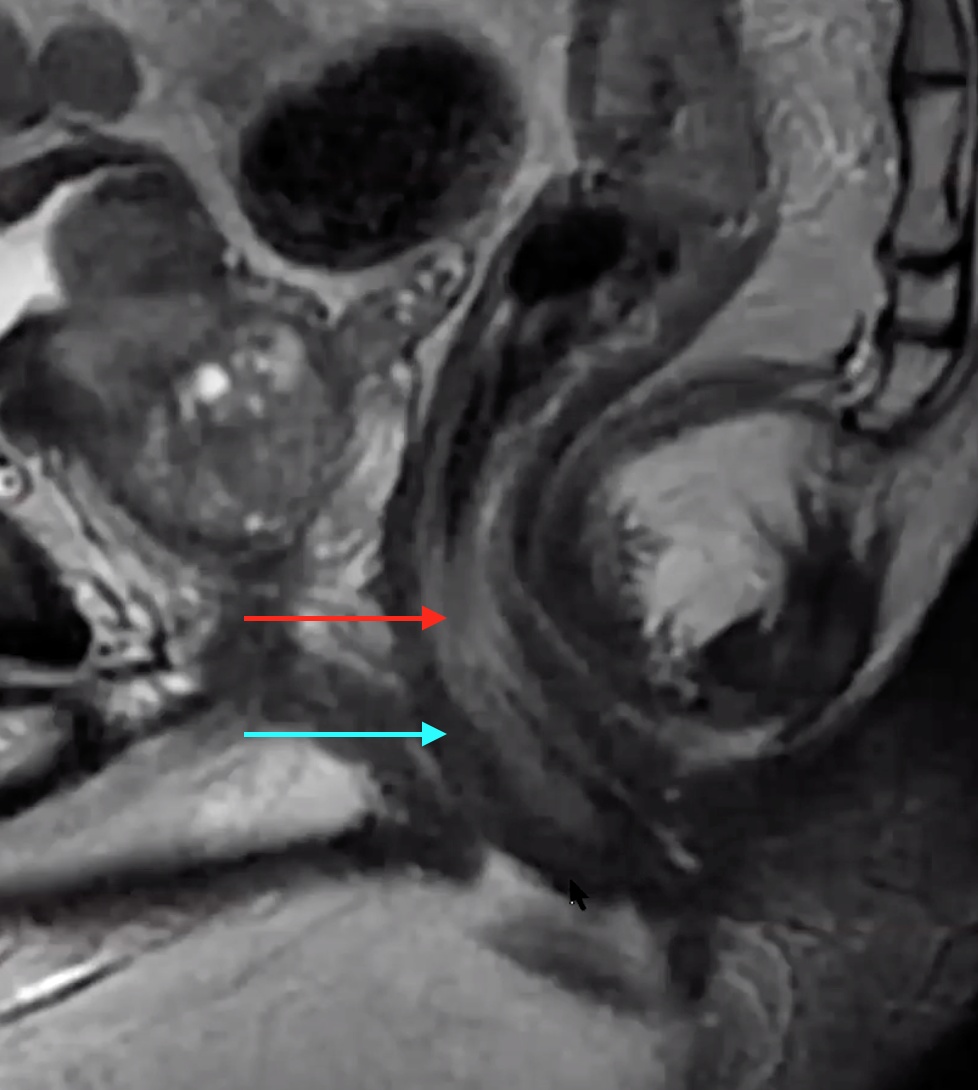

Mesorectal Fascia

• Thin dark line surrounding the mesorectal fat

• Like a tear drop shape

• Superiorly ends at the level of the recto-sigmoid junction where it blends into the sigmoid mesentery

• Inferiorly blends into the puborectalis and levator muscles

• Wide in the center

Puborectalis

• U shaped muscle on either side

Peritoneal Reflection

• Thin dark line that has a bend in it anterior to the rectum

Iliococcygeous